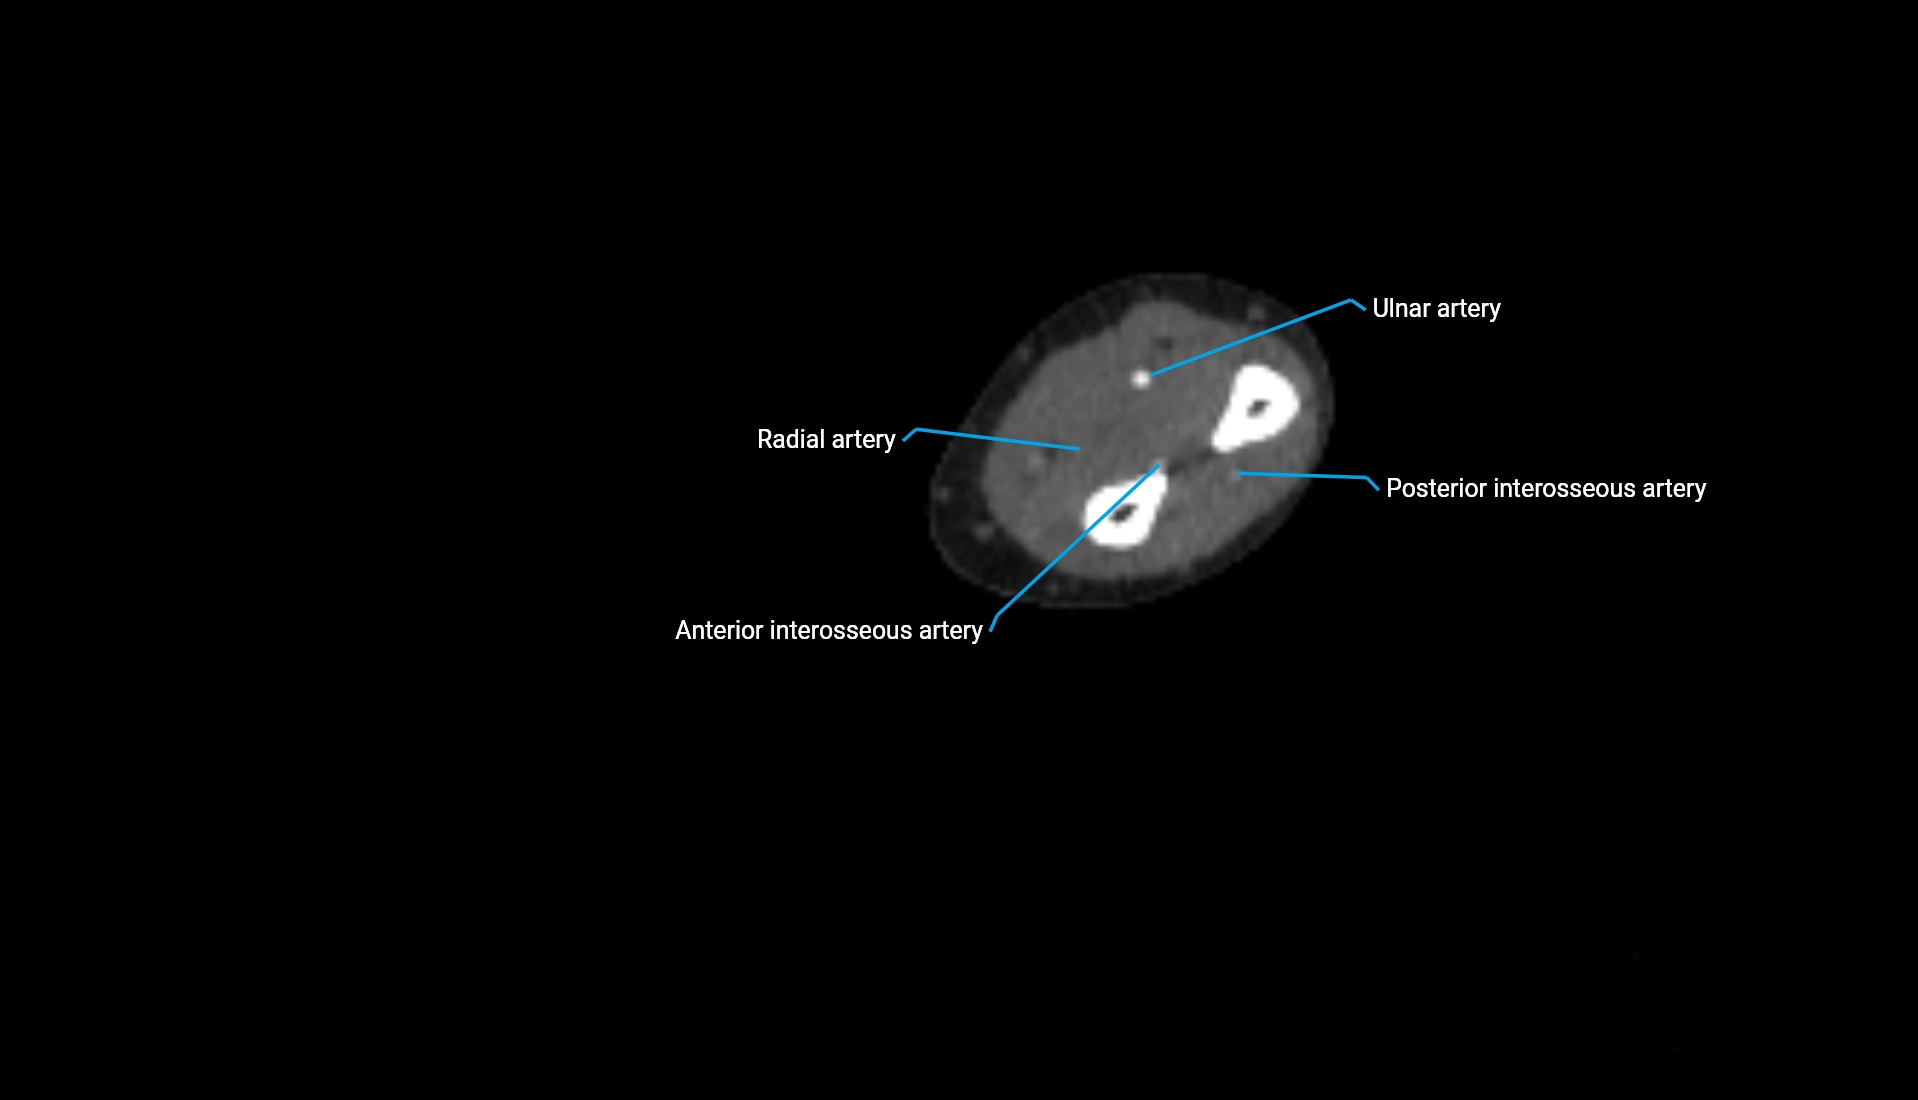

CT Appearance

Non-Contrast CT:

• Cortex: High-density, sharply defined

• Subchondral bone: Dense cancellous matrix

• Articular surface: Smooth concave contour articulating with the capitellum

• Excellent for evaluating bone integrity, alignment, and subtle fractures